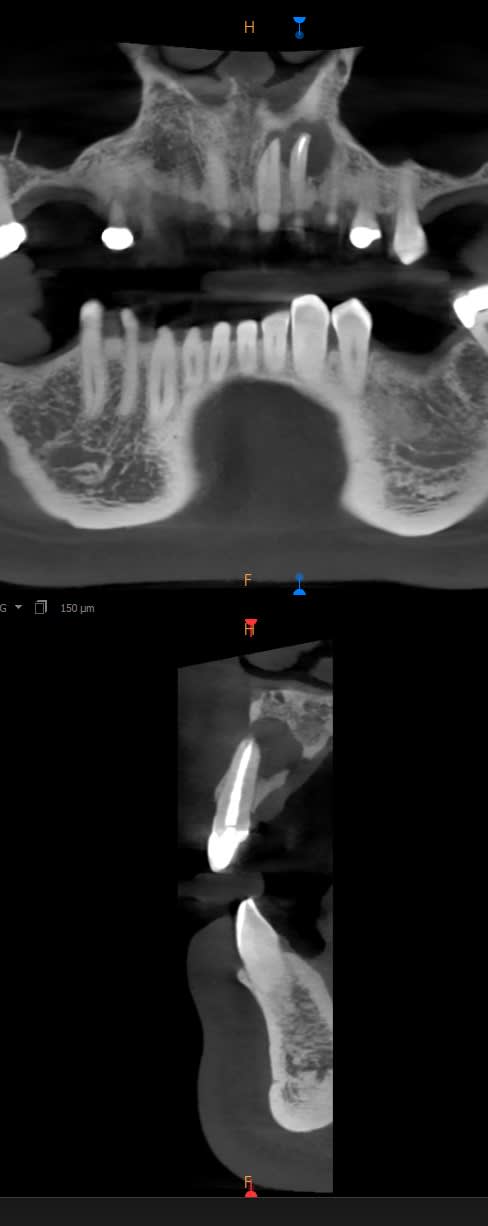

Ce patient m'a été adressé aujourd'hui car sensibilité au palais en regard de la 22.

Je ne vois aucune fissure ou défaut d'obturation au niveau de la 22. La 21 est sans signe clinique, vitale.

Je suis parti pour l'extraction de la 22 (nous n'avons pas d'endo spé chez nous).

Autre conduite à tenir selon vous?

Au vu de la coupe frontale j'aurais dit pourquoi pas tenter une ERI chère à enlaye mais faut reconnaître que sur la vue transversale la pauvrette a plus trop d'os et certainement plus beaucoup de ligament pour récupérer une attache.

La corticale vestibulaire est vraiment pas top.. et me paraît très "collée" à la racine.

Pas impossible qu'elle vienne avec la dent

La 22 n'est clairement pas conservable à long terme.

Par contre elle peut être conservée provisoirement avec une résection sévère (au moins moitié de la racine) dans le cadre d'un curetage+comblement, pour essayer d'éviter un greffe ultérieure compliquée, qui sera inévitable si extraction d'emblée. En effet, si extraction en l'état la corticale vestibulaire ne tiendra pas le choc, et peut-être même en palatin...